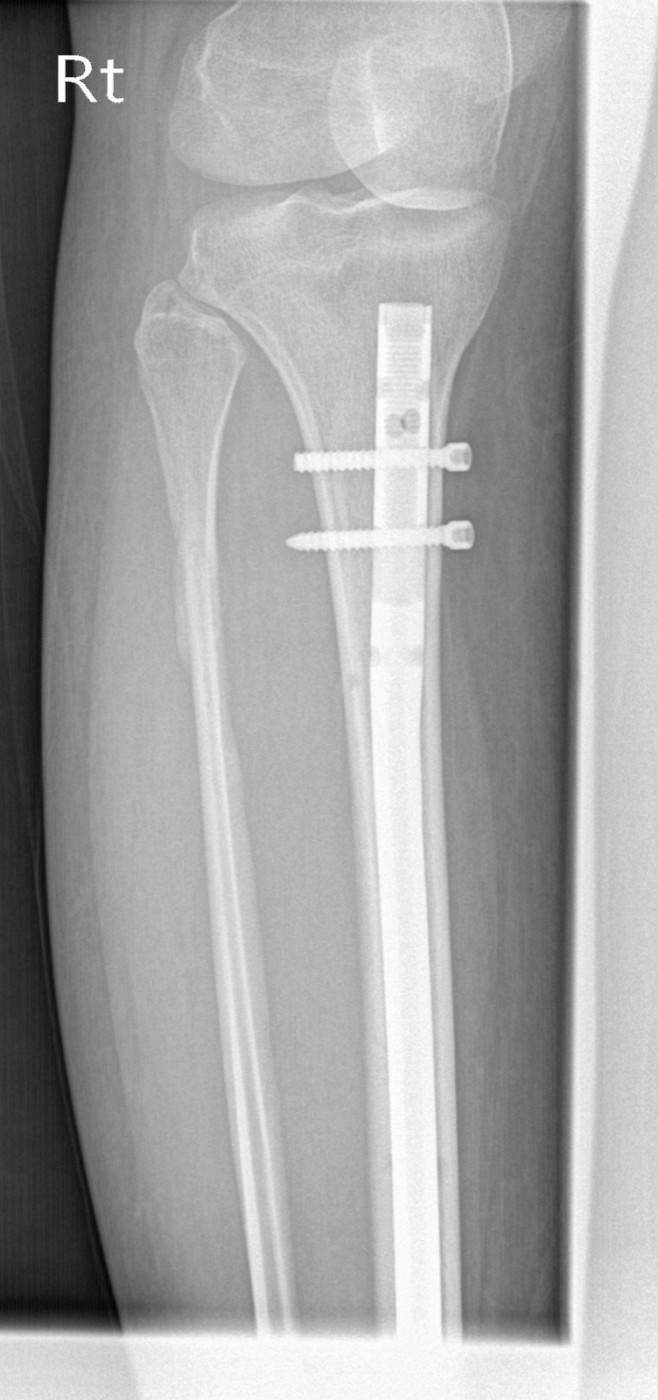

Перелом внутренней лодыжки у ребенка